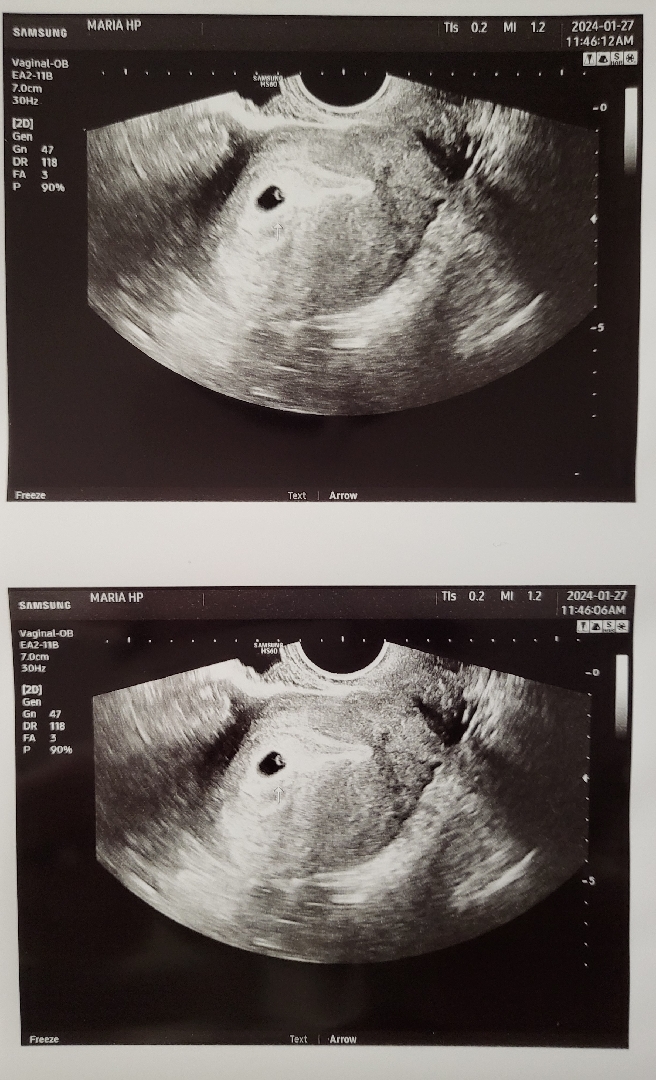

4주 6일 아기집 난황 보고 왔어요!

4주 6일 아기집 난황 보고왔어요! 아기집 크기같은건 이야기 못들었고했는데 아가집 모양 위치 괜찮은걸까요~ 결혼 5년만에 생긴 아가라 그런지 사진 한장에도 아주 걱정 한가득이네요~